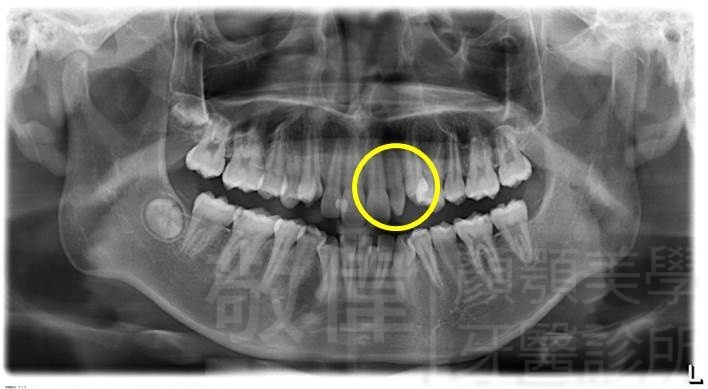

| 8 | 前牙美容 | 快速矯正之美容晶瓷貼片及晶鑽瓷冠 | ||